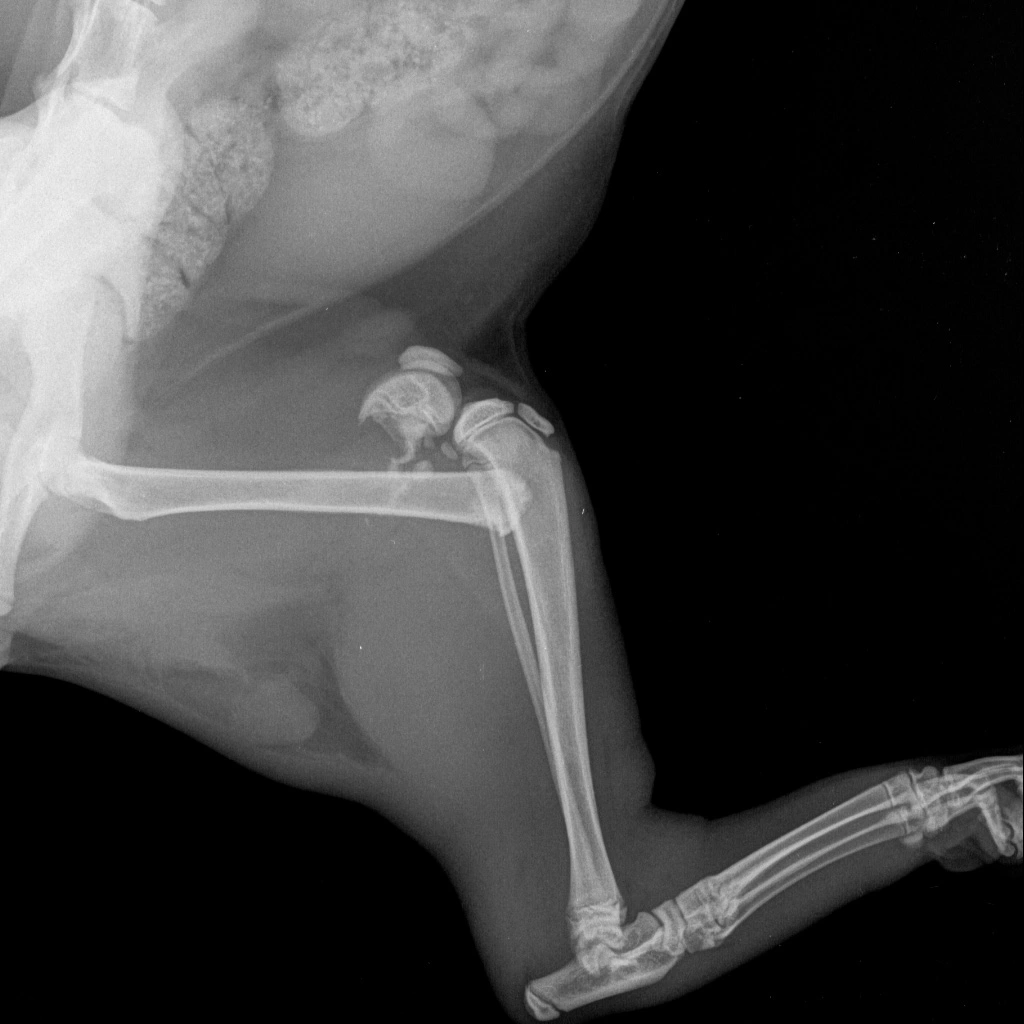

Каждый пациент и его ситуация индивидуальны. При выборе лечения нужно учитывать огромное количество факторов, таких как вид перелома, его сложность, сопутствующие заболевания и многое другое. Для полного заживления перелома необходим комплекс оптимальных условий: полное сопоставление отломков, высокая жесткость их фиксации, сохранение функции и кровоснабжения поврежденной кости и конечности. За последнее время методы фиксации переломов постоянно совершенствуются и на сегодняшний день гипсовые повязки практически не используются в ветеринарной практике, что позволяет адекватно и быстро реабилитировать больных животных.

При поступлении животного в ветеринарную клинику врач в первую очередь оценивает общее состояние животного и если животное находится в состоянии, которое не угрожает жизни, то производится диагностика повреждения при помощи рентгенографии (рентген костей), рентгеноскопии или компьютерной томографии (КТ) и дальнейшее лечение перелома. При состоянии, которое угрожает жизни, проводится ряд мероприятий интенсивной терапии, при которых животное «стабилизируется» в независимости сколько для этого потребуется времени, чтобы быть готовым к проведению остеосинтеза (хирургической операции по соединению отломков костей при помощи различных фиксирующих конструкций обеспечивающих стабильную фиксацию отломков в правильном положении).

В зависимости от расположения и типа фиксатора различают внутренний остеосинтез (погружной, накостный, интрамедуллярный, чрескостный) и наружный чрескожный (метод Илизарова и его модификации). Выбор метода хирургического лечения перелома определяет ветеринарный врач исходя из особенностей травмы, сложности перелома, индивидуальных особенностей животного (размер, возраст, состояние костной ткани, темперамент).

- Рентгенография: позволяет визуализировать изменения в костной ткани, такие как уменьшение плотности костей и их деформацию.

- Компьютерная томография (КТ): позволяет получить более детальные изображения костей и выявить даже маленькие изменения.

Классификация переломов

По времени возникновения переломы бывают: врожденные и приобретенные. Врожденные возникают в утробный период жизни вследствие травм матери или в результате сильных сокращений матки. Предрасполагают к таким переломам внутриутробные патологические изменения костной системы – рахит, аномалии развития плода, остеомаляция у матери.

Приобретенные переломы возникают или в момент рождения, например, при родовспоможении, или, чаще всего, уже после рождения на протяжении всей жизни. Они подразделяются на травматические и патологические (или самопроизвольные), т.к. они, как правило, происходят без видимых механических усилий.

По характеру повреждения переломы бывают: открытые и закрытые.

По анатомическому характеру различают переломы диафизарные, эпифизарные или внутрисуставные и метафизарные. По течению заболевания самые неблагоприятные – это эпифизарные переломы, так как они могут привести к нарушению функции сустава.

По характеру повреждения переломы бывают неполные и полные. Неполные переломы характеризуются частичным нарушением целостности кости. К ним относятся: трещины, надломы, отломы, поднадкостничные переломы, дырчатые переломы или пробоины.

Если нарушение целостности кости происходит в одном месте, то такой перелом называется одиночным, в двух местах – двойным. Может быть и множественный перелом.

Полные переломы характеризуются полным разъединением кости на всю ее длину или ширину. В зависимости от положения линии излома к продольной оси кости выделяют следующие виды переломов: поперечный, косой, продольный, спиральный, зубчатый, вколоченный, оскольчатый, раздробленный, размозженный, отрывной.